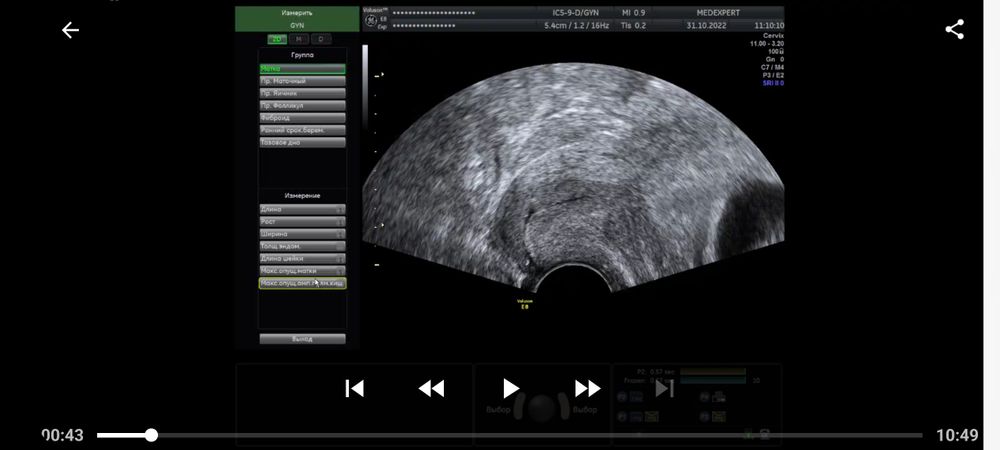

Ретрохальная гематома и мягкая шейка 9 недель беременности

9 недель и 3 дня срок. Сегодня сделала узи, по причине того, что в прошлый раз была отслойка 11×3мм (заключение прикладываю). В результате сегодня имеем прогрессирующую отслойку 27×3мм. Помимо этого шейка матки очень мягкая и губы свободно двигаются при перемещении датчика. Иногда тянет живот, не сильно, как перед месячными, только намного слабее. Выделения по цвету немного желтоватые, но не постоянно, а раз за несколько дней. А так, нормальные по цвету, без запаха. Кровяных или коричневых выделений нет. Прием у акушера-гинеколога только завтра. Приговор врача-узи заставляет нервничать и переживать, но пытаюсь отвлечься и успокоиться, была озвучена угроза прерывания беременности. Приехала домой и соблюдаю постельный режим до завтрашнего дня. Встаю только по крайней необходимости (туалет, покушать). Из препаратов ничего не принимаю, только витамины Элевит первый триместр. Как мне вообще вести себя в данной ситуации до приема врача? Чего бояться и при каких ситуациях вызывать скорую. Короче я напугана.